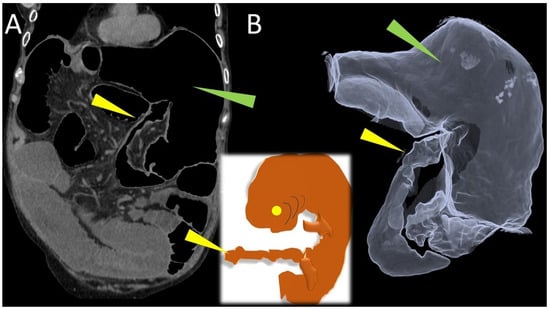

The CT scan also revealed the characteristic mesenteric whirl signs, a dilated cecum with an air/fluid level, marked overdistension with air-fluid levels of the small bowel and the collapsed appearance of the entire colon (Figure 2 and Figure 3). The cecum becomes tangled in the mesenteric vortex, just like a tissue woven paper along its longitudinal axis by opposing rotary movements of the hands.

Figure 2. Coronal (A) CT image demonstrates a vortex composed of the cecum entangled on its longitudinal axis and a spiral of mesenteric vessels (yellow arrow) rotating consensually with the cecum: the “whirl” (red arrowhead). Seen along the longitudinal course, the entangled cecum (red arrowheads in (B,C)) contains small hypodense areas between its collapsed and intertwined walls, which represent mesenteric tissue incarcerated by the spiral braid of the cecal walls (green arrowheads in the yellow box).